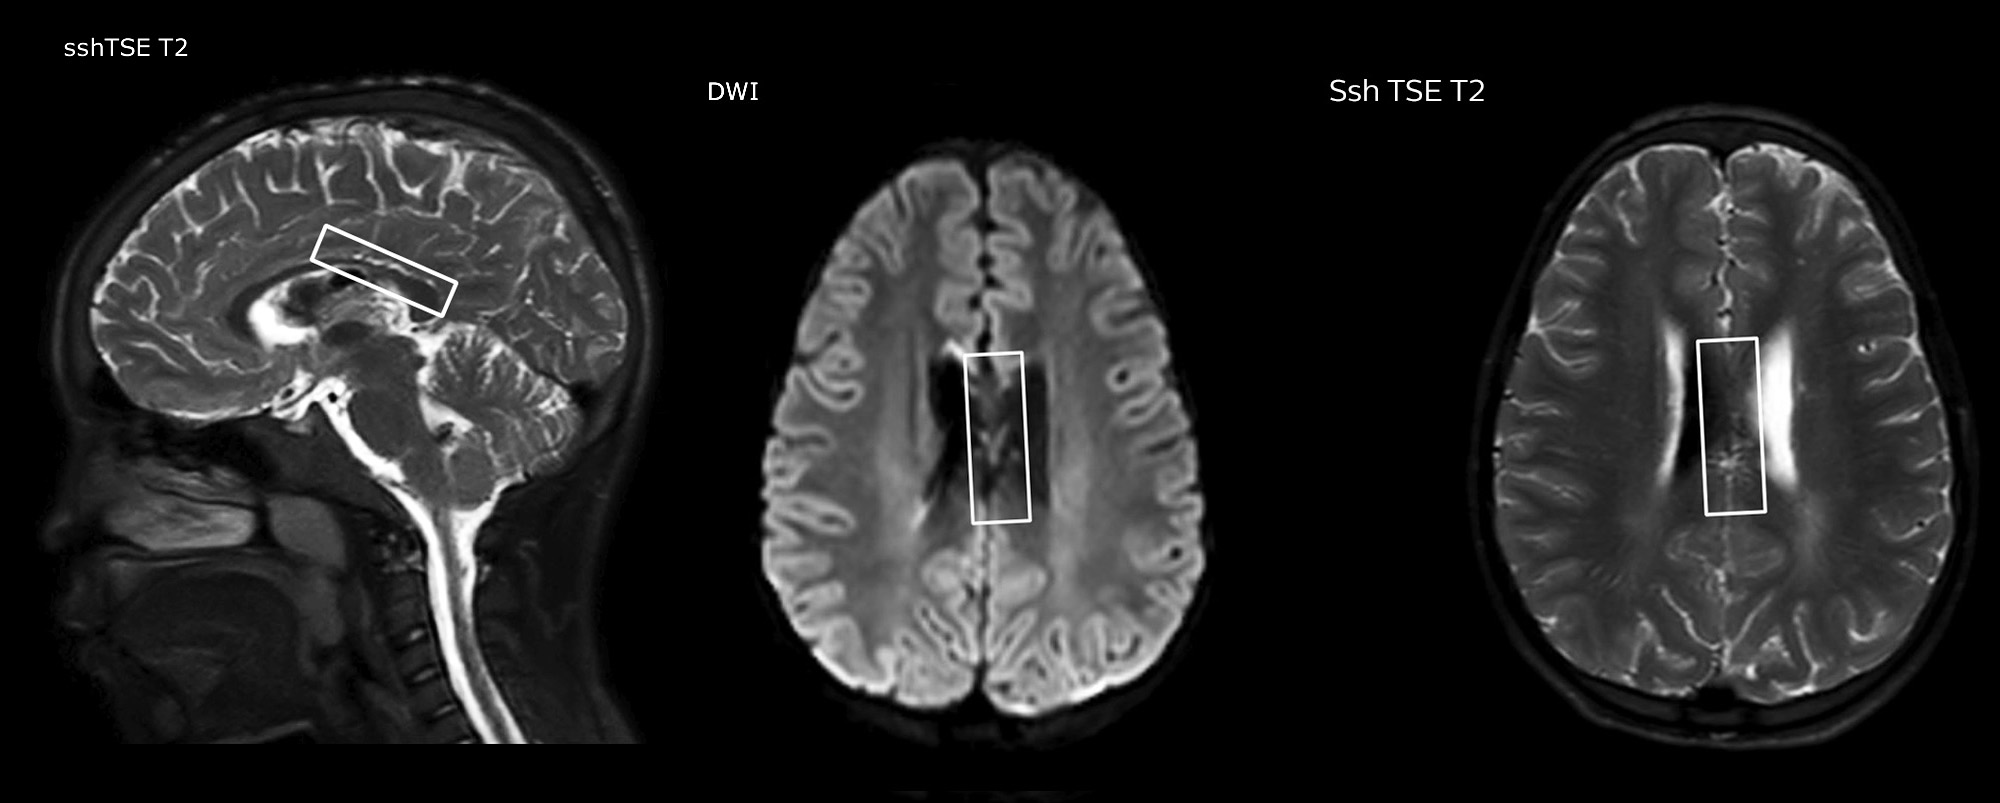

“In combination with diffusion weighted imaging, it can help give a more extended assessment of the degree of perfusion abnormality in a patient who is suffering acute ischemia. We have a number of patients who have chronic arterial insufficiency due to prior arterial abnormalities or acquired arterial abnormalities such as sickle cell disease or neurofibromatosis. Sometimes the child’s first manifestation of disease progression is a reduction in brain perfusion before stroke symptoms manifest clinically or in diffusion weighted imaging. We use pCASL to help delineate the perfusion abnormality.”

To other new users I would recommend to also start to interpret the pCASL images in comparison with other standard imaging – T2 and FLAIR and DWI – until the user gains confidence in interpreting these images by themselves.”